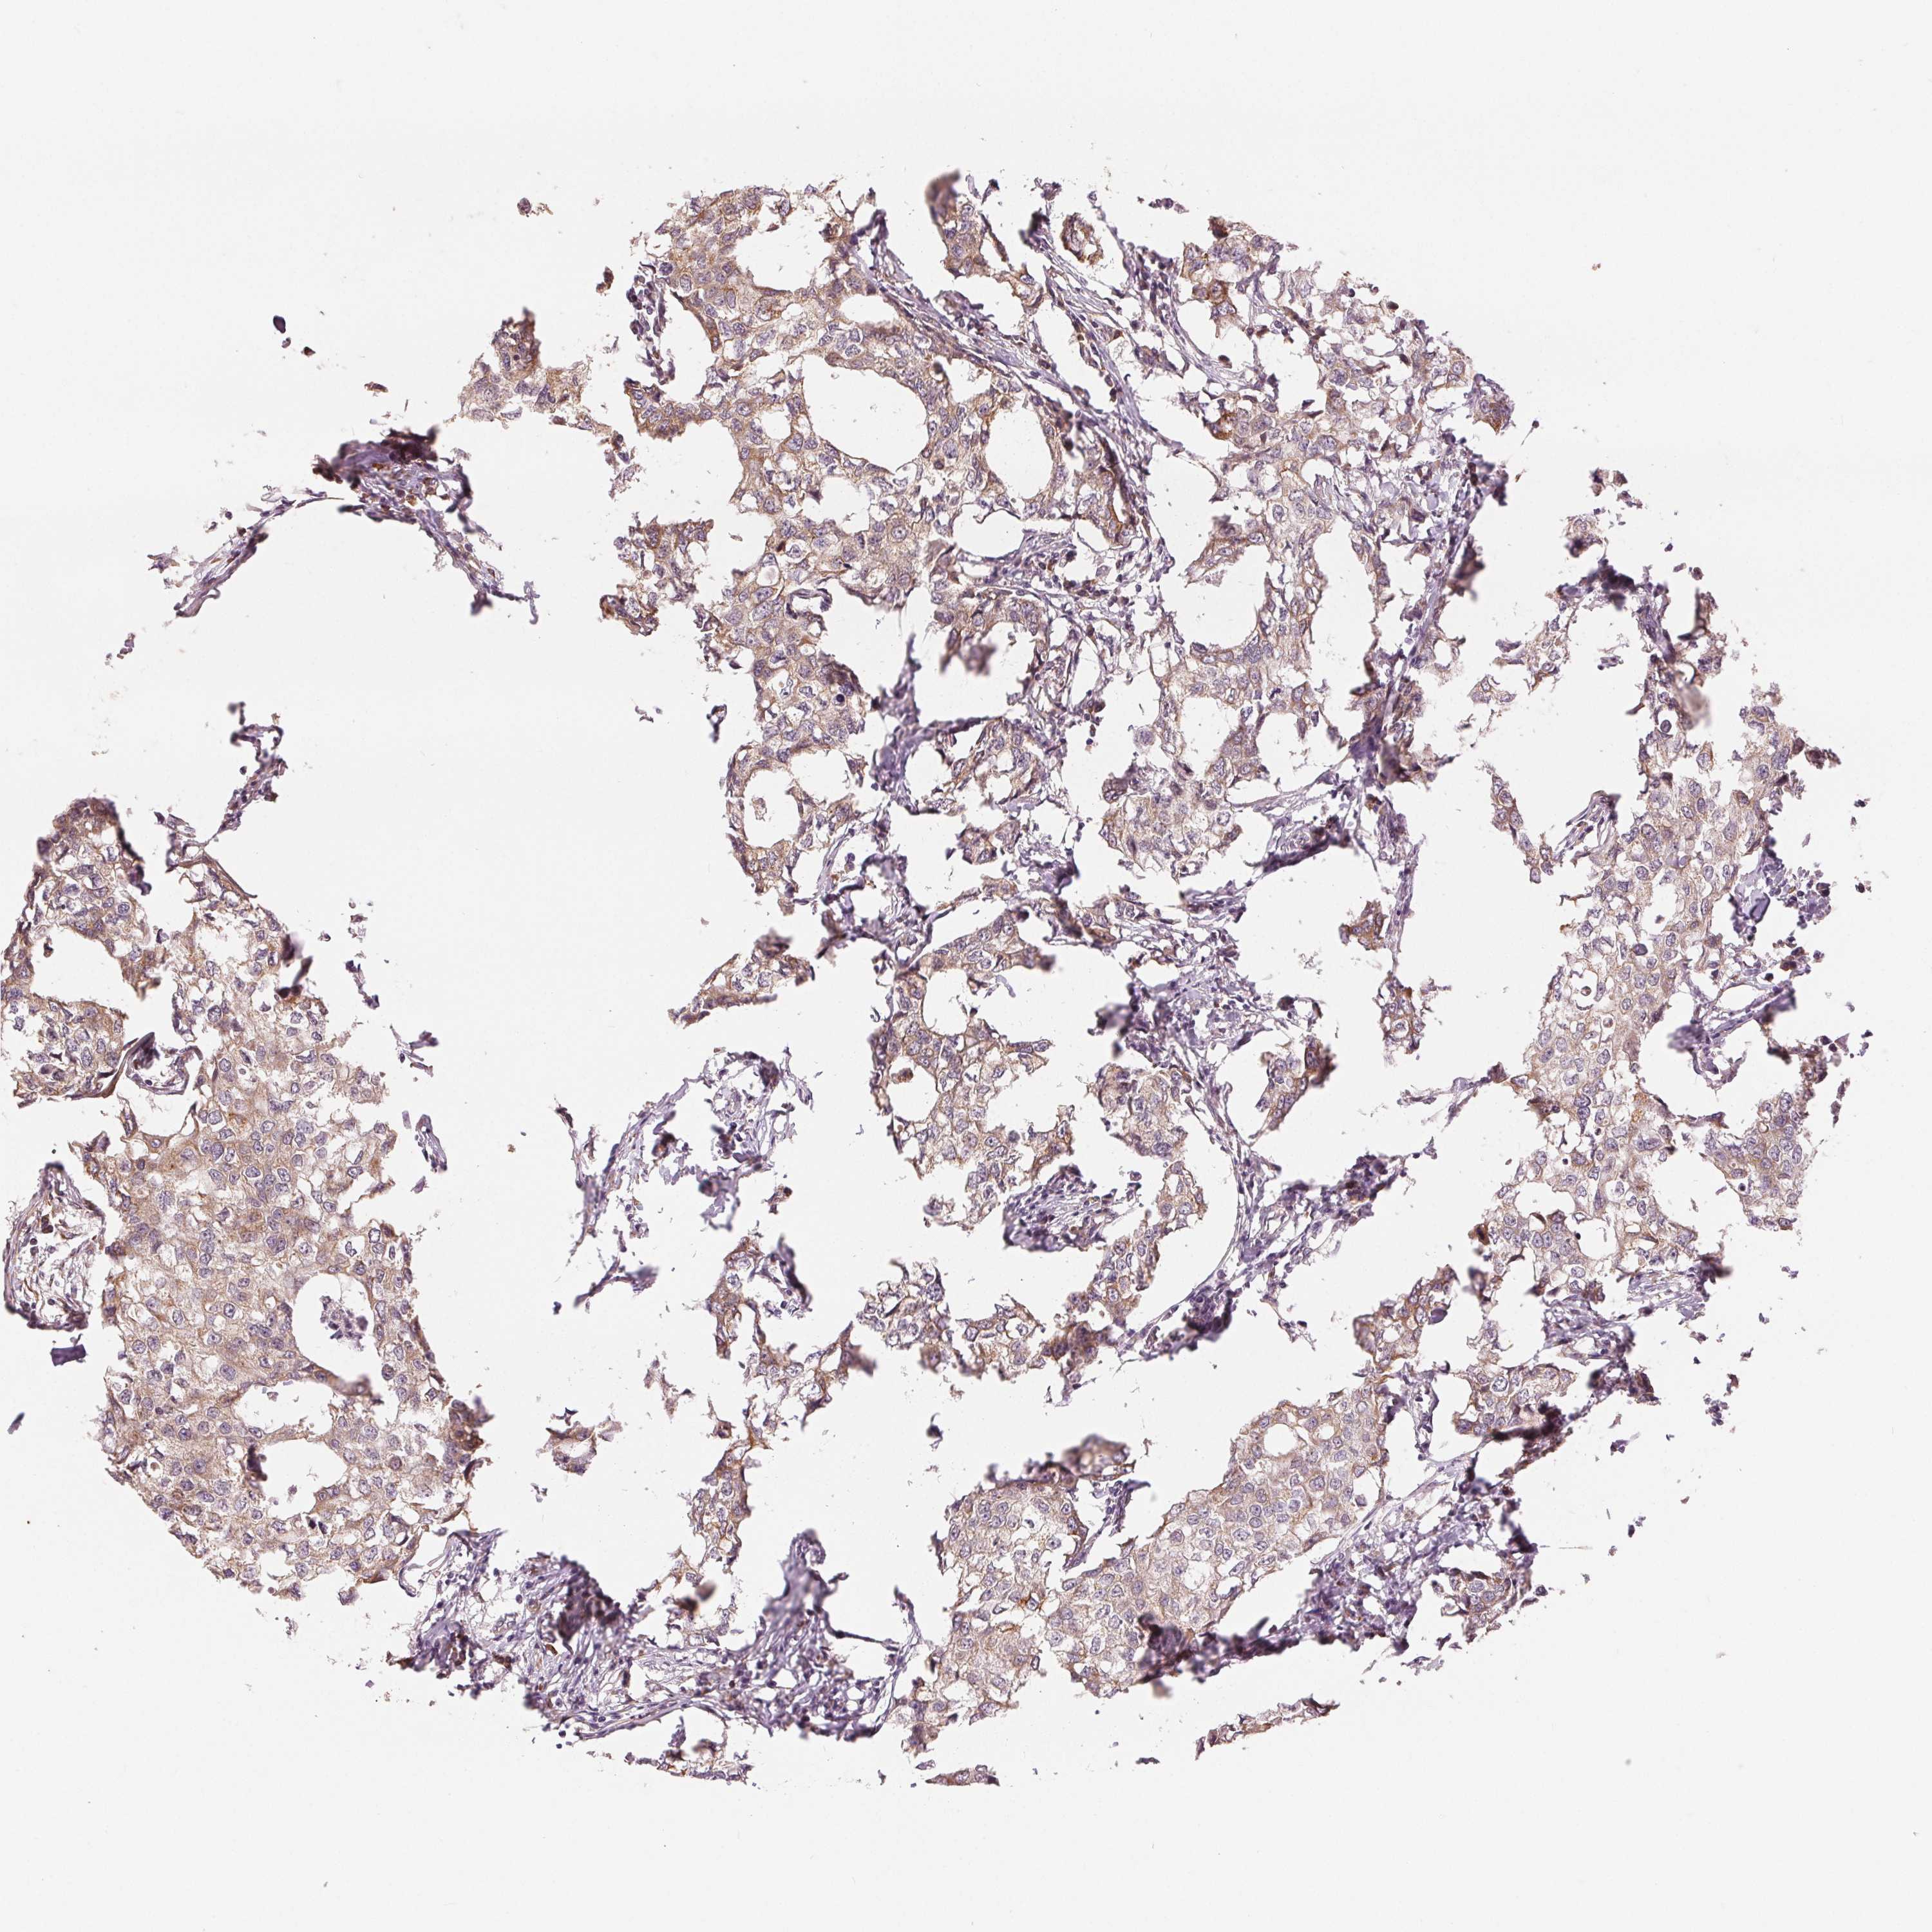

CANCER BREAST CANCER Show tissue menu

BRCA TCGA BRCA VALIDATION PROTEIN EXPRESSION